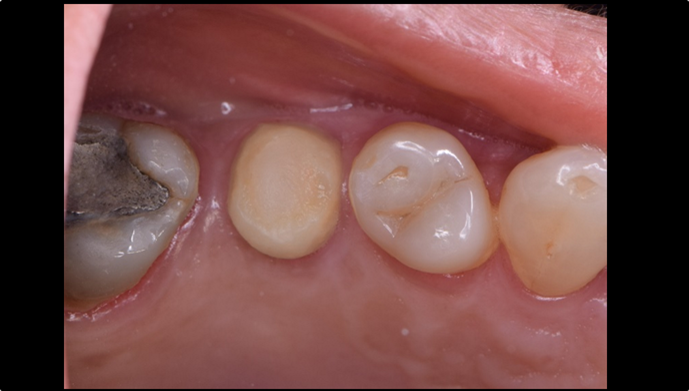

Clinical case: R2GATE GUIDE surgery with GBR

- Courtesy of Dr. Kwang Bum Park, Korea -

Dr. Kwang Bum Park, digital guided surgery, bone regeneration, maxillary posterior, #13, #14, guided surgery, GBR, AnyRidge, i-GEN, Mega-Oss, R2GATE, R2GATE Full surgical kit